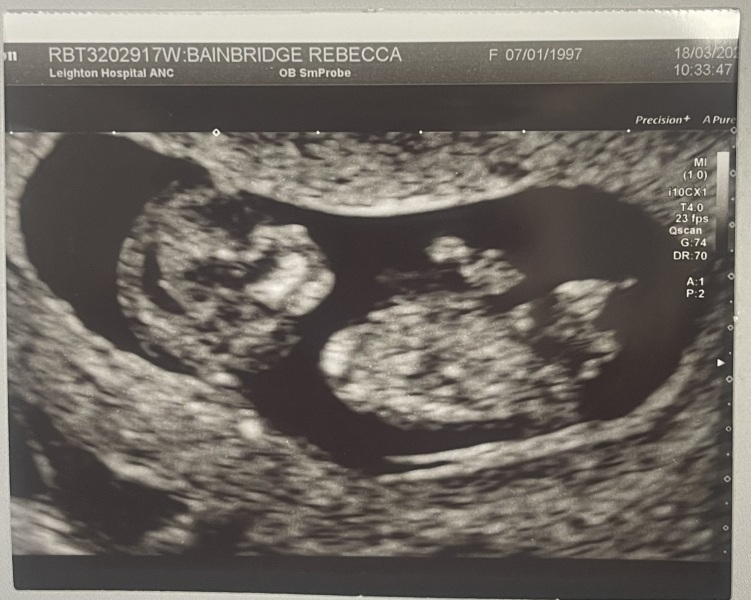

Beck208 · 26/03/2024 20:34

@tryforbabynumber2 bet your over the moon 2 bundles of joy ! 🤩 my first who is 6 now, was a boy and didn’t show until 20+ weeks all the others have been girls and shown straight away, even tho I got past 20 weeks there all angels, I got my rainbow baby girl last October, and made it to 33 with her I was absolutely massive 🤣 keep worrying in the back of my mind so thing isn’t right for not showing, but everything was perfect when I had my 12 week scan, are these your first baby’s ? Xxx

Hi everyone! Had a scan yesterday at 10+4 and measuring exactly on schedule! Baby has grown so much! Also did my NIPT test so in for a long wait with the bank holidays!